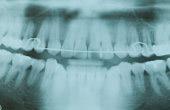

На рентгенограмме выраженная утрата кости в результате пародонтита.

Достижение максимального эстетического эффекта начинается с правильной установки имплантатов. Для этого необходимо сделать точную рентгенограмму.